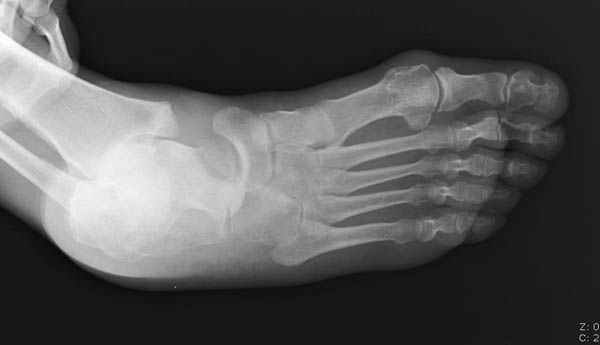

Уважаемые участники русского Ортофорума, поздравляю всех со всеми прошедшими праздниками: Новым годом, Рождеством, Hanukkah, Kwanzaa, желаю участникам всего наилучшего и здоровья.Повреждение таранной кости.Больной 81г автоавария, повреждение таранной кости, здесь снимки. Какие рекомендации?Djoldas Kuldjanov, MDDepartment of Orthopedic SurgerySt. Louis University Medical Center

Вдогонку по поводу перелома таранной кости, больная 81, не страдает диабетом, перелом закрытый, в первый же день поступления ограничились временным наружным фиксатором (как на снимке).

Планировалась открытая фиксация после спадения отека, но больная пожелала лечиться по месту жительству в другом штате..

За пару недель насчитал 5 больных с переломом таранной кости, из них двое с двусторонним повреждением.

Из-за отека на стопе тактика лечения у всех была

одинаковая: временная наружная фиксация до спадения отека, при изолированных переломах они выписывались домой и через дней 7 госпитализировались на оперативное лечение.

Примеры на снимке...